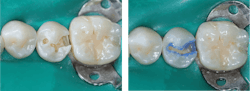

The following procedures are suggested for all classifications of resin-based composite use. The most popular burs for typical initial class I and class II restorations are #330 for the isthmus width of a molar and #329 for the isthmus width of a premolar or diamond rotary instruments of similar size and shape (figures 1 and 2).

Normal depth tooth preparation. After making the tooth preparation, etch it using your preferred procedure (total etch, selective etch, or self-etch). I prefer selective enamel etch of enamel only, but any of the three ways works. Etch 15 seconds in a nonfluoride area, or 20 seconds in a geographic area with community water fluoridation (figures 3 and 4).

Continue with placing bonding agent and restorative resin of your choice. The brands of bonding agents and restorative resins have become very similar since composite resin has been in use since the late 1950s. According to CR surveys, the Solventum (3M) products are most popular (Scotchbond Universal Plus and Filtek Supreme Ultra). Other widely used brands are Kerr, Ivoclar, GC, Dentsply Sirona, and many others.